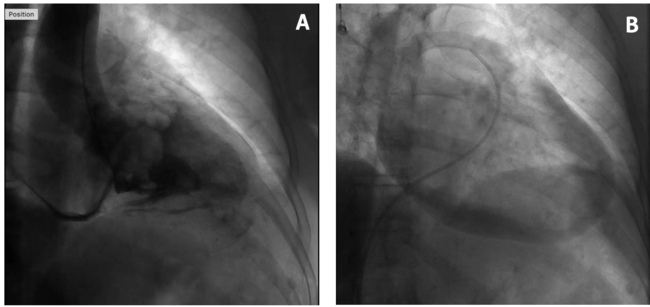

Left ventricular perforation is a rare complication of myocardial infarction, cardiac trauma, or due to an iatrogenic cause, such as cardiac catheterization, biopsy, temporary or permanent pacing, or pericardiocentesis. We present a case of a 79-year-old woman who underwent a left heart catheterization complicated by catheter-induced ventricular perforation. The aortic valve was difficult to cross with a 0.035-inch regular J-tip wire. A 5-Fr AL2 catheter and 0.035-inch regular straight wire were used instead. The AL2 catheter was then swapped with the straight pigtail catheter. The left ventriculogram showed normal left ventricular function with dye opacification into the pericardial cavity, outlining the pulmonary artery, aorta, and left atrium (Figure 1; Video Series), consistent with intraprocedural ventricular perforation with consequent hemorrhagic pericardial effusion (Figure 2; Video Series). The patient was hemodynamically stable initially, however, ~45 minutes post procedure, her systolic blood pressure reduced to 50 mm Hg. Right heart catheterization revealed cardiac tamponade physiology. Emergent pericardiocentesis was performed and 400 mL of frank blood drained. The patient was stabilized and sent to a cardiothoracic center for pericardial patch repair for the probable perforation. She remained stable and contrast echocardiogram confirmed the absence of persistent communication between the left ventricle and the pericardium.